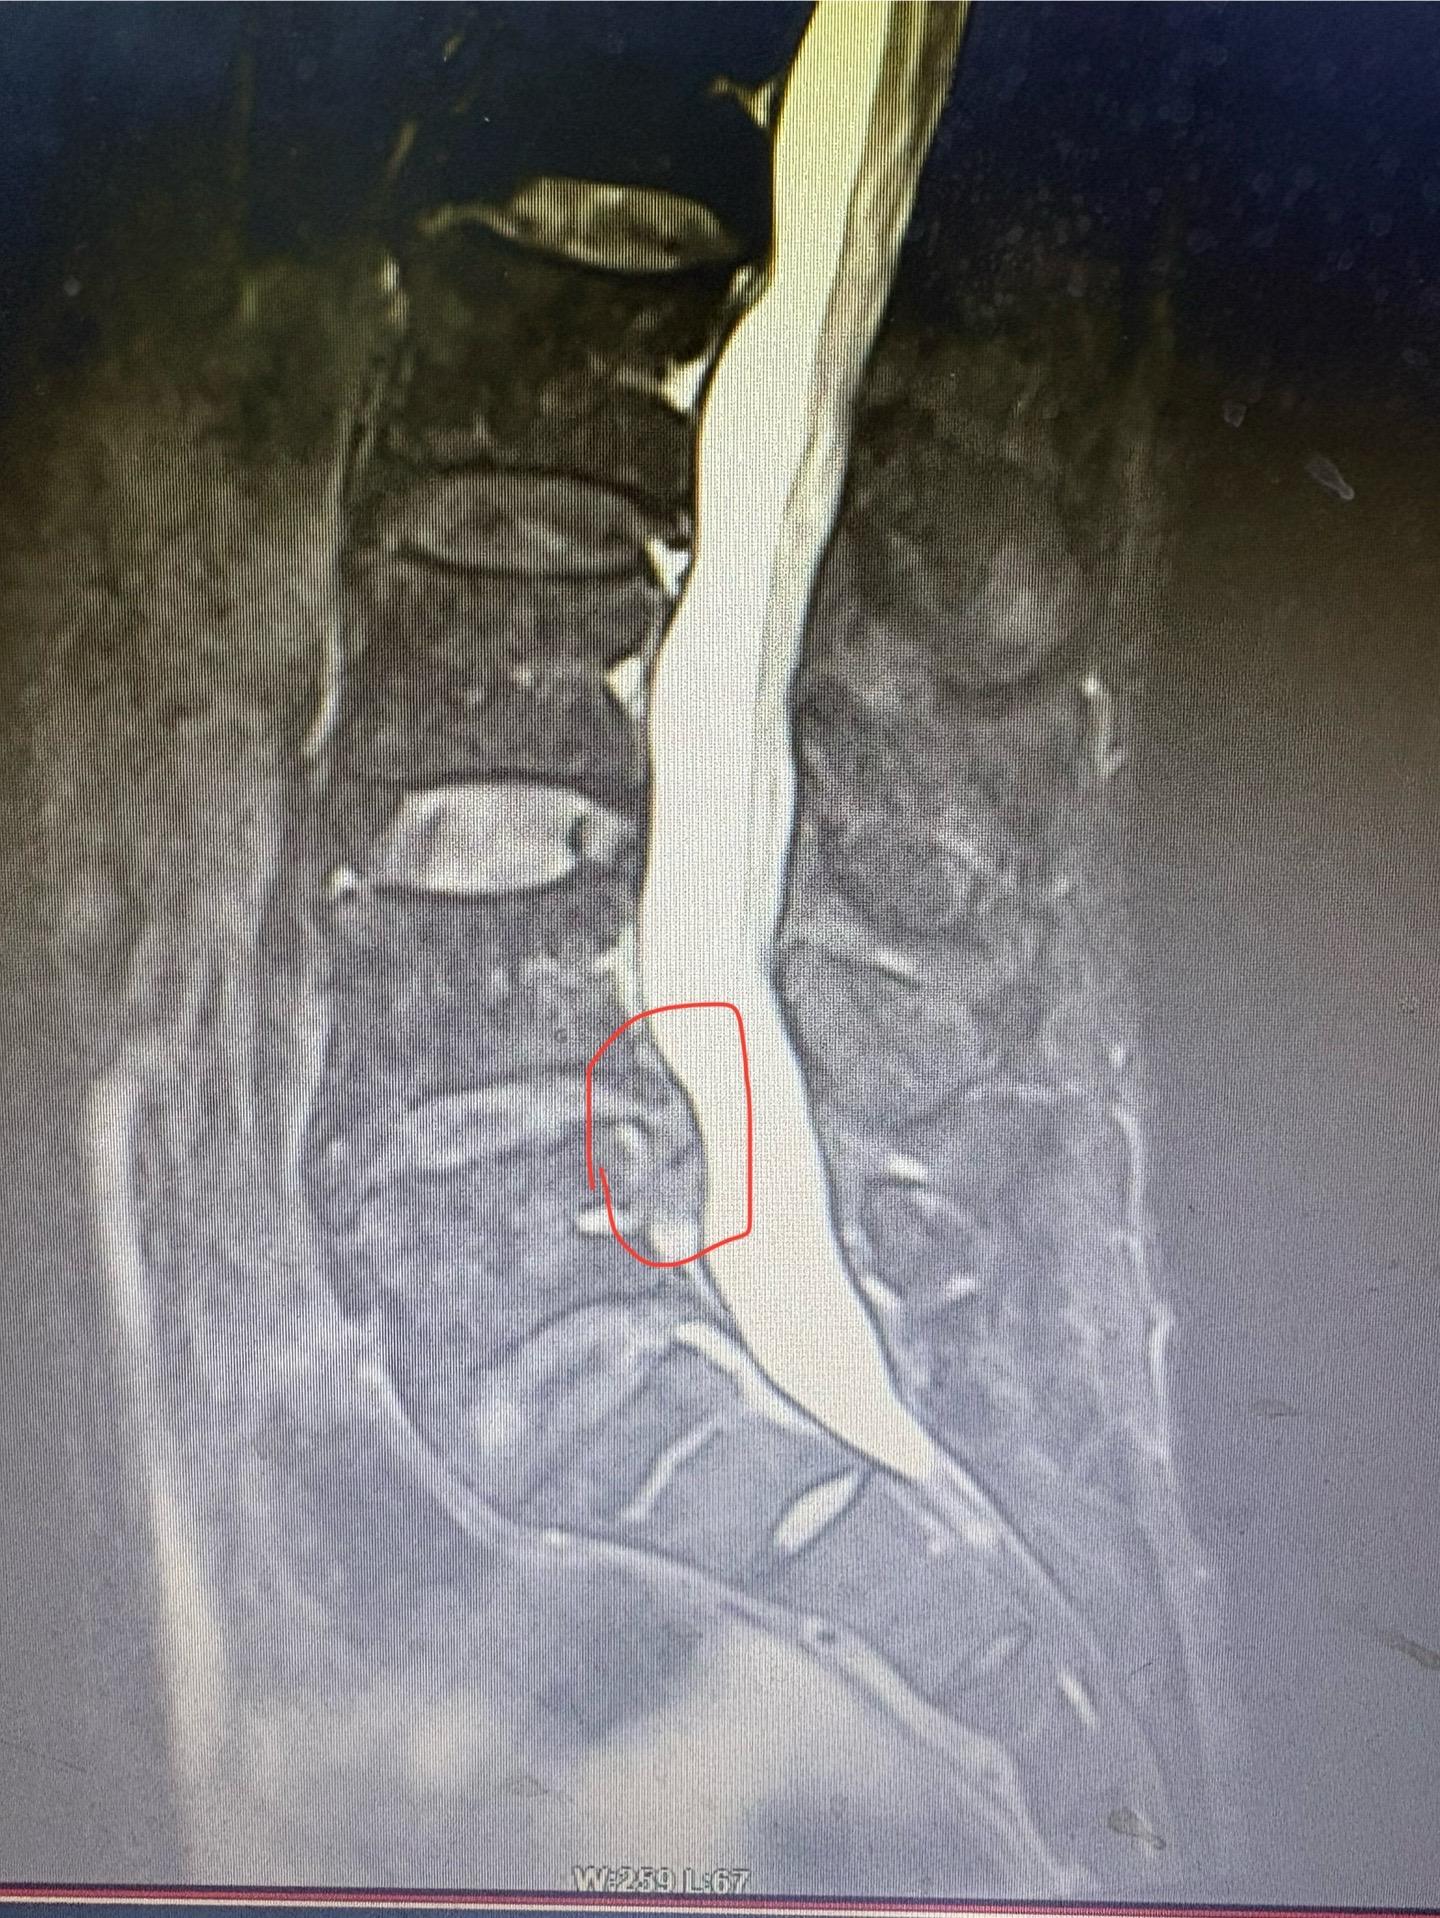

脱出的腰椎间盘,选择局麻的内镜手术也是可以的,但是也有可能会残留,需要...